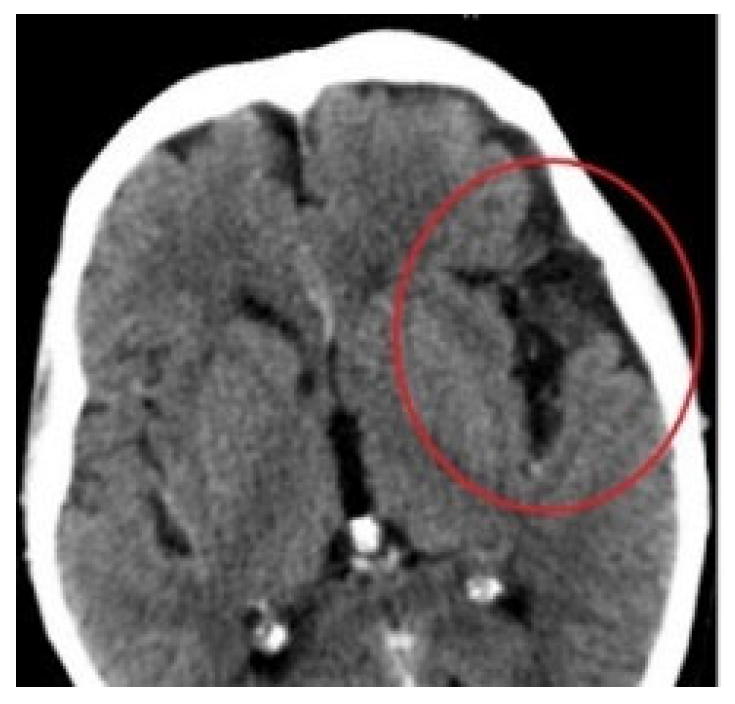

The patient underwent a non-contrast CT scan (Revolution Evo system, 64 rows, GEHealthcare). The obtained image revealed a defect of bone and soft tissue in the glabella area, about 3 cm in diameter, and an overgrowth of bone tissue across the entire width of the nasofrontal duct. (Figure 3A,B)

Figure 3. (A) Condition after the first CT scan-sagittal plane. (B) Condition after the first CT scan-transverse plane. (C) CT scan 14 days after first procedure-sagittal plane. (D) CT scan 14 days after first procedure-transverse plane.

Fourteen days following the laryngological procedure, the created canal was found to be overgrown and the nasofrontal duct lacked patency. A repeat CT scan of the facial part of the cranium confirmed that the canal was overgrown with soft tissue compared with the previous examination (Figure 3C,D).

Another medical case meeting was held, this time with specialists in neurosurgery and maxillofacial surgery. Frontal sinus obliteration was planned: however, a defect was noted in the posterior wall of the frontal sinus (Figure 7) together with a 10 mm-wide fluid space in the temporoparietal region (Figure 8) with a density of 15 Hounsfield units, a dilated Sylvian fissure. Therefore frontal sinus cranialization was eventually proposed.

Figure 7. Defect in the posterior wall of the frontal sinus, CT scan.

Figure 8. Fluid space in the frontotemporal region, CT scan.